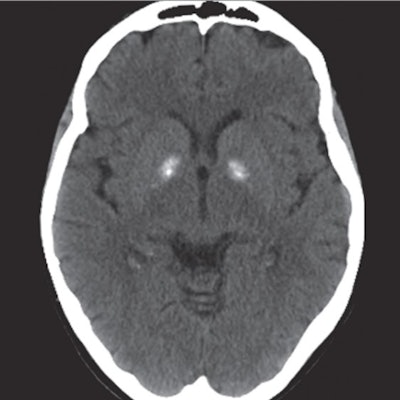

All year, CT helped illuminate more surprising manifestations of COVID-19 and track its transmission. A team from the University of Maryland School of Medicine in Baltimore found that nonchest CT exams performed at the behest of emergency department physicians often also captured pulmonary findings suspicious for COVID-19. In addition, Temple University Health System researchers shared a case of a woman who was diagnosed with the illness when she underwent CT staging for breast cancer.

But CT isn't just for common applications: It also plays a key role in the diagnosis of rare illnesses or conditions. In particular, this past year CT helped clinicians solve the case of a tourist to Cuba who developed symptoms of neurological impairment after her trip. The symptoms were similar to those of U.S. and Canadian diplomats in Cuba in 2016; the diplomats' symptoms were originally thought to be caused by a "sonic weapon" but turned out to be due to pesticides.